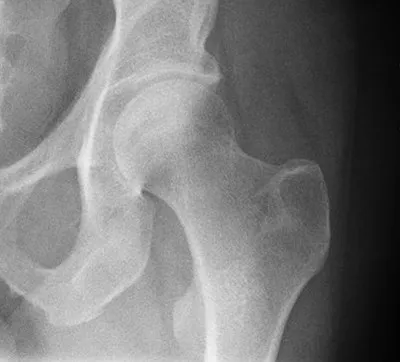

Section titled “Pain in the Hip”To give another example, here's the CT of a heavy equipment operator's hip joint.

A normal hip joint (Wikipedia)

On the upper left is the pelvic bone with its socket-style hip joint. Rising from the lower right is the top of the femur with its ball fitting into the socket.

The radiologist read this as irregular contour of the acetabular (hip) joint, with mild to moderate osteoarthritis.

In English, this means that both the ball at the top of the femur and the socket in the pelvic joint, which should have smooth surfaces, do not.

OK, his hip joint was not perfect, but I've seen worse. However my patient's pain was rendering him unable to complete his work responsibilities. In fact he was having pain so severe it would drop him to the floor without warning. In addition, he was self-employed and unable to work, so he took a significant financial hit.

While opiates are a curse for many people, they can be a blessing for others and they were a blessing for him for a few days while the acute pain subsided. Once we had achieved that, I sent him to a physical therapist. She looked at the image above and told him that she was not certain that the physical therapy would be all he needed. She left open the option of surgery should her methods not suffice. He too, like the skier, was of a compulsive nature and did the exercises she taught him, as regularly as a monk goes to prayer.

Within two weeks he was back on his excavating equipment and within six weeks was out in the mountains hiking, as was his habit. The last I heard, he'd ascended the steep, rugged trail up Mount Tyler with no difficulty or pain whatever.